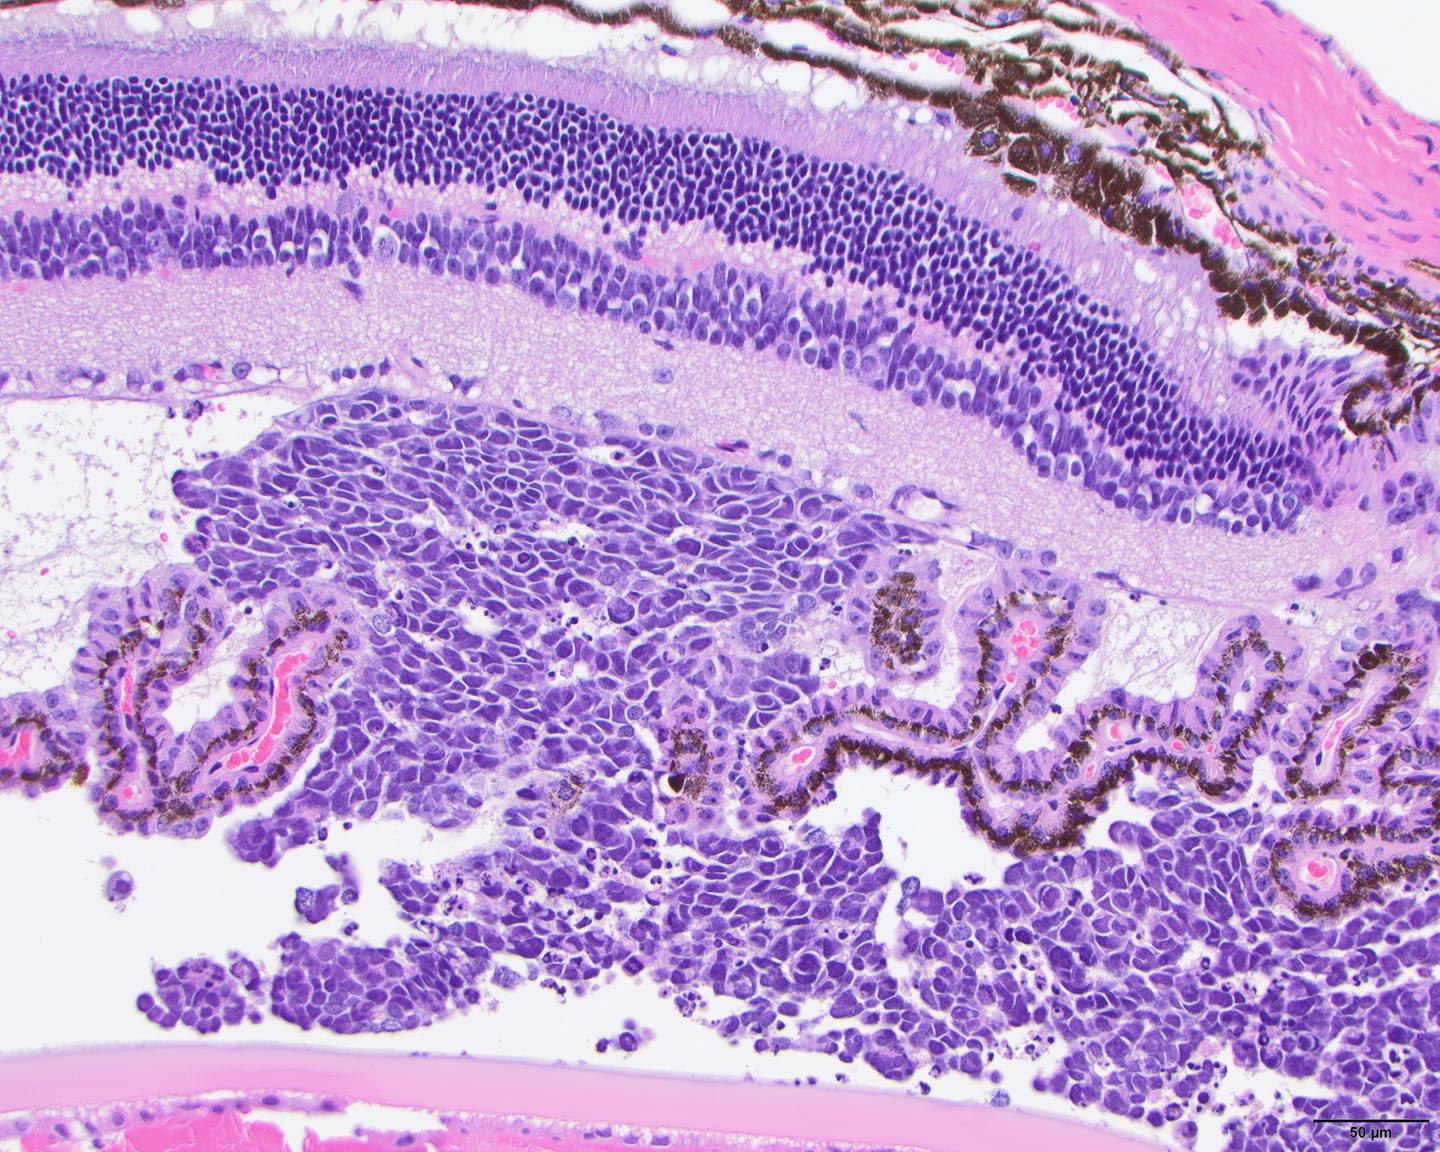

A human tumor that is grown in a mouse or other animal is called a xenograft. It is most commonly implanted by injecting tumor cells just under the animal's skin. Instead, Dyer's team wanted to grow their tumors in the relevant tissues; these tumors are called orthotopic xenografts. The researchers knew that a tumor's development is influenced significantly by its microenvironment in the body.

Dyer's team then compared the molecular and cellular features of the mouse tumors to those of the patient tumors from which they were derived. Many of the mouse tumors retained the complex makeup of the patient tumors, the researchers found.

"We know that cancer isn't a homogeneous population of tumor cells. It's a mixture of different cells," Dyer says. "For at least some of the patients, we're able to capture that complexity." This is important, because a tumor's cellular composition can change dramatically after treatment, and the cells that persist largely determine whether a patient's cancer recurs, he says. "With the xenografts, we can for the first time model this complexity in the laboratory."